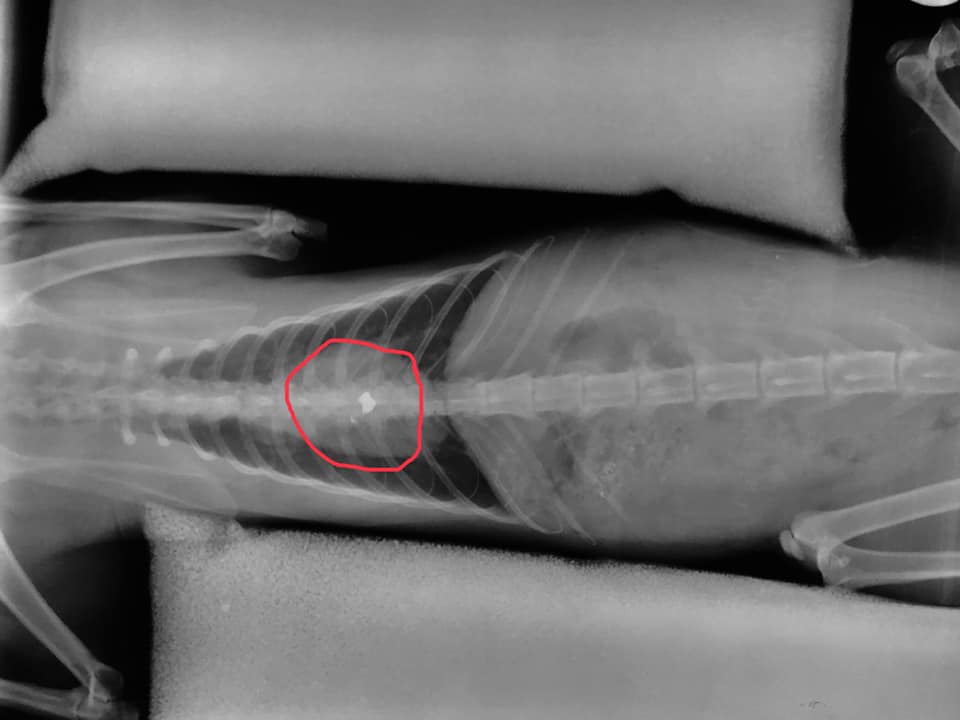

Το σφαιρίδιο στην σπονδυλική στήλη του ζώου.

Η γάτα αρχικά είχε μεταφερθεί στους κτηνιάτρους Μπατίκας Δ. – Μόσχος Γ. αλλά καθώς δεν είχαν ακτινογραφικό μηχάνημα στη συνέχεια μεταφέρθηκε στο κτηνιατρείο της Έλενας Σωτηρίου και εκεί οι ακτινογραφίες έδειξαν το σφαιρίδιο του αεροβόλου σφηνωμένο στην σπονδυλική του στήλη.